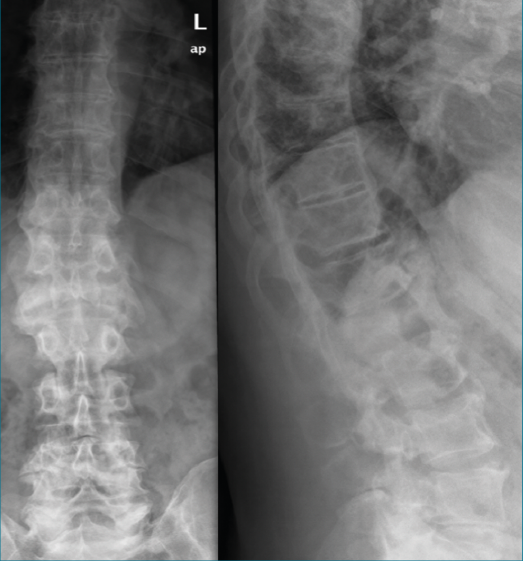

Se realiza una radiografía lumbosacra anteroposterior y lateral (Figura 1) en la que destaca un aplastamiento importante a nivel del cuerpo de L1.

Figura 1. Radiografía de columna dorsolumbar. Aplastamiento del cuerpo L1.